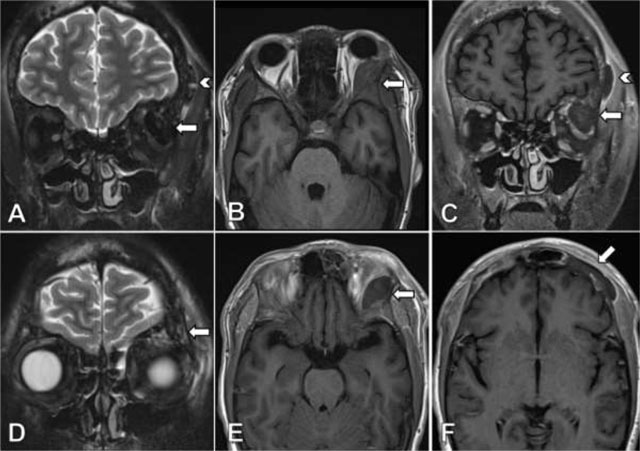

Figure 2

Coronal TSE T2-weighted image with fat suppression (A) shows a markedly hypointense lesion located in the lateral aspect of the left orbital roof (arrow) and a second lesion lining the external table of the frontal bone on the left side (arrow head). On axial TSE T1-weighted images (B) the lesion exhibits a isointense signal compared to the adjacent bone, without lesional enhancement after injection of gadolinium (E). Coronal contrast-enhanced TSE T1-weighted image (C) reveals a faint perilesional enhancement, more prominently in the lesion lining the frontal bone on the left (arrow head). Coronal TSE T2-weighted image with fat suppression (D) shows asymmetrical, discrete bone edema and prominent nonenhancing lesions on contrast-enhanced TSE T1-weighted image (F) in the frontal bone on the left side compared to the right side.

A 19-year-old male patient with the homozygous sickle cell trait was admitted to the hospital due to a sickle cell crisis. His main complaint was unbearable pain in the extremities. The patient’s history was remarkable for multiple previous admissions for sickle cell crises. During his admission he developed a swollen left eye, with discrete ptosis of the upper eyelid and minimal exophthalmia. There were no visual disturbances and eye movement was unimpaired. A contrast-enhanced computed tomography (CT) of the orbits showed a lens shaped extraconal mass lining the lateral wall of the left orbit (Figure 1). The lesion measured 3.1 × 1.2 cm with high attenuation due to enhancement or spontaneously dense compounds. The underlying frontal and sphenoid bones were unremarkable. The patient was referred for MRI the same day for further work-up. The lesion was markedly hypointense on T2-weighted images with fat suppression (Figure 2A). T1-weighted sequences showed an isointense signal comparable to the adjacent bone (Figure 2B). There was no lesional enhancement after injection of gadolinium and faint perilesional enhancement (Figure 2C). Imaging findings were compatible with an acute subperiosteal orbital hematoma (SOH). Additionally, MRI revealed a new extracranial subperiosteal hematoma lining the external table of the frontal bone on the left side (Figure 2C). This hematoma was less hypointense on T2-weighted images and exhibited more prominent perilesional enhancement. The frontal bone and left greater wing of the sphenoid bone showed discrete bone oedema on T2-weighted images (Figure 2D) and asymmetrical low signal intensity on contrast-enhanced T1-weighted images (Figure 2F), suggesting areas of infarction. The patient received supportive treatment after diagnosis, and the eye swelling diminished spontaneously over time.

Imaging is important for the differential. Our patient received prompt CT and MRI evaluation on the same day. Although the lesion was hyperdense on CT, we could not be sure if this represented blood or contrast enhancement as only contrast-enhanced CT was performed. The signal characteristics on MRI of this nonenhancing lesion combined with the acute clinical presentation were compatible with an acute hematoma, hence the diagnosis of a subperiosteal hematoma. The markedly T2-hypointense signal made a neoplastic lesion less likely.